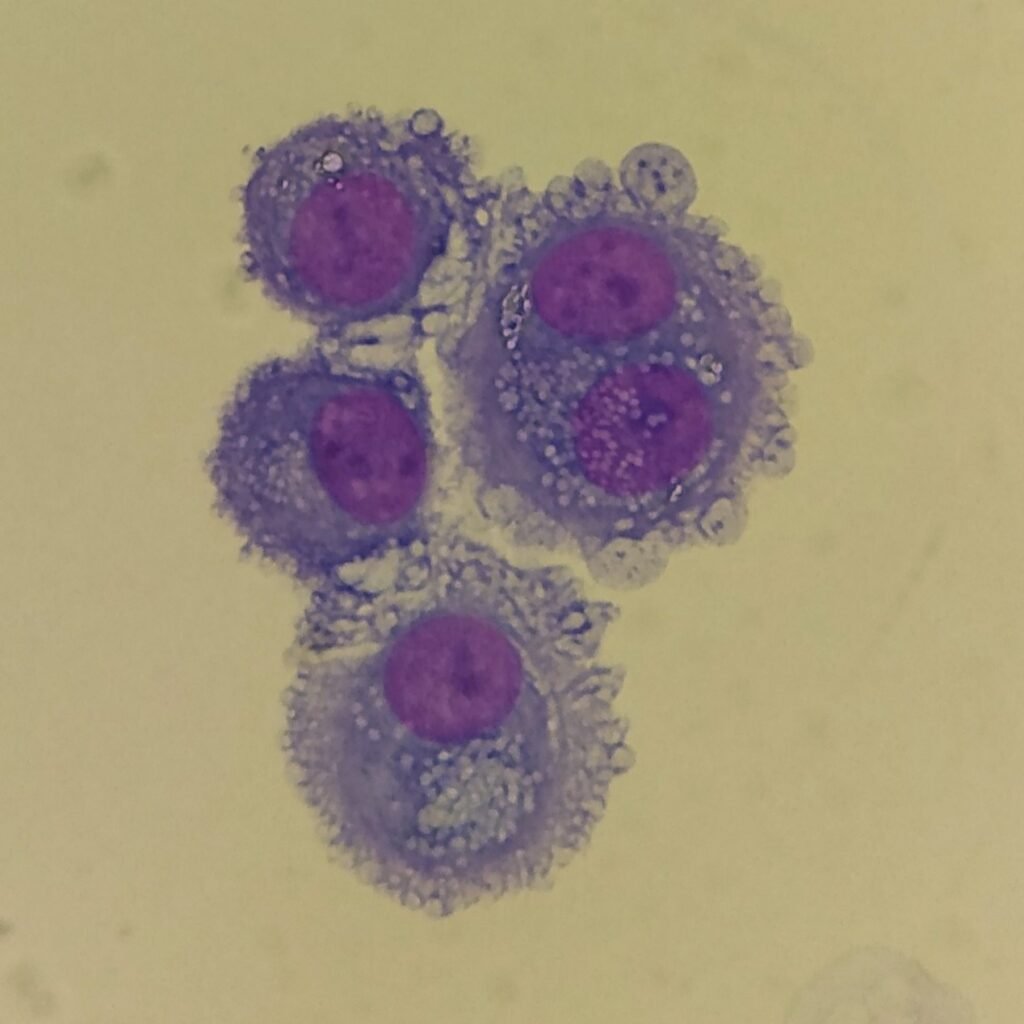

Mesothelial cells are described as having a “fried egg” appearance. They have a round to oval nucleus with smooth borders and evenly distributed chromatin. Nucleloli are usually present. Mesothelial cells may also be multinucleated.

Cells may be seen in clumps, but “windows” between cells still allows for individual counting.

Both malignant cells and mesothelial cells can clump together. However, malignant cells will not have the windows between cells.